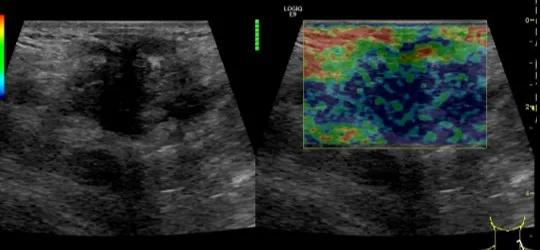

第三例是甲状腺癌患者,双侧甲状腺癌切除术后、碘治疗后一年余效果欠佳,超声显示左颈3区3枚低回声结节,穿刺示甲状腺乳头状癌转移。患者不愿意手术,希望采取局部治疗。对病灶进行液体隔离后采取热消融术,由于淋巴结较小,热消融一分钟左右完全灭活,术后增强影像显示没有脏器充填。

(病例3图例)